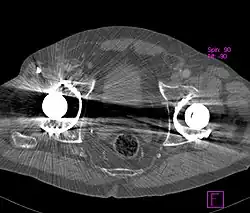

Die Röntgenröhren, die in der Computertomographie verwendet werden, arbeiten mit typischen Beschleunigerspannungen zwischen 80 und 140 kV. Die dabei emittierte Röntgenstrahlung weist ein breites Energiespektrum auf. Durch die Strahlaufhärtung ist dieses Spektrum nun nach Durchdringen des Objekts (Patienten) zu höheren Energien hin verschoben. Die Strahlaufhärtung ist dabei umso stärker, je länger der Weg durch das Objekt ist oder je höher die Elektronendichte der einzelnen Schichten ist. Die heute in der CT verwendeten Detektoren sind nicht energieauflösend, d. h., sie unterscheiden nicht zwischen Photonen unterschiedlicher Energie. Die einzelnen Detektorelemente messen stattdessen nur die in ihnen deponierte Gesamtenergie, was einer Mittelung über die Photonenenergien entspricht. Durch diese Mittelung geht ein Teil der Informationen verloren, was letztlich die Ursache für die Aufhärtungsartefakte darstellt. Unkorrigierte CT-Bilder weisen einen typischen Verlauf auf, bei dem die Grauwerte zum Zentrum (Rotationsachse des CT) hin dunkler werden.

Sieht man CT-Bilder vom Menschen, ist es schwierig zu entscheiden, was echt ist und was ein durch Strahlaufhärtung erzeugter Artefakt. Eine Möglichkeit, das zu differenzieren, besteht in der Verwendung eines Phantoms. Es handelt sich um menschliche Knochen, aber die Weichteile sind durch Wasser ersetzt. Das Phantom erlaubt es, die vom Knochen verursachten Verfälschungen der CT-Werte in den benachbarten Weichteilgeweben quantitativ abzuschätzen. Sie sollten idealerweise 0 Hounsfield-Einheiten betragen. Durch den Aufhärtungseffekt entstehen in dem die Weichteile simulierenden Wasserbad teils hypodense, teils hyperdense Artefakte.